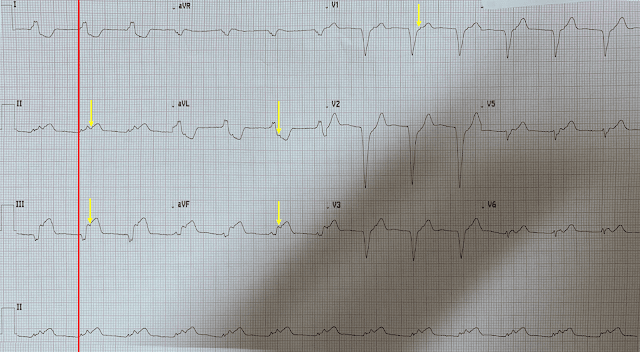

81-летняя женщина с анамнезом терминальной стадией болезни почек, а также гемодиализом, нормальным радионуклидным стресс-тестом годом ранее, малоинвазивной замены аортального клапана и приемом варфарина, фибрилляцией предсердий, диастолической сердечной недостаточностью, ожирением, диабетом, гипертонией и инсультом были доставлены в отделение неотложной помощи по поводу нарушений психики и гипотонии, которые начались ближе к концу сеанса диализа. По прибытии скорой помощи в ее диализный центр специалистам не удалось измерить артериальное давление. Была записана догоспитальная ЭКГ, которая выглядела идентичной исходной ЭКГ при поступлении, показанной ниже, и врач скорой, обеспокоенный состоянием пациентки и ее ЭКГ, позвонил врачу клиники и спросил, следует ли планировать экстренную катетеризацию:

Что бы вы сказали?

Интерпретация ЭКГ

- Синусовый ритм, АВ-блокада 1-й степени, частые предсердные или узловые экстрасистолы (вызывающие несколько периодов регулярно нерегулярного ритма)

- Длительность QRS составляет приблизительно 0,1 с, с морфологией, предполагающей блокаду передней ветви.

- Диффузная депрессия ST, максимальная в V4-V6 и отведении II, с обязательной реципрокной элевацией ST в aVR

Впечатление

Находки согласуются с диффузным несоответствием потребности и доставки без признаков фокальной окклюзии. Как мы много раз объясняли в этом блоге, дифференциальный список при такой картине ЭКГ огромен и включает неокклюзионный ОКС (например, острый левый главный ОКС, болезнь трех сосудов с неокклюзионной причиной) или любую причину, не относящуюся к ОКС, любая из причин (или вместе) снижающие доставку или увеличивающие потребность. Список причин для этой последней возможности слишком длинный, чтобы перечислять его снова, но общие причины включают гипотонию, гипоксемию, сепсис, желудочно-кишечные кровотечения и т. д.

Элевация ST в aVR с диффузной депрессией ST НЕ является диагностическим признаком поражения левой главной или тяжелого поражения трех сосудов. Чаще это характерно для диффузной субэндокардиальной ишемии или несоответствия потребности и доставки. Причины такой находки обширны и включают сепсис, гипоксию, ТЭЛА, тахикардию, желудочно-кишечные кровотечения и т. д. А также ОКС. Это практически полностью зависит от клинической ситуации.

Обратите внимание, что это контрастирует с депрессией ST в отведениях V1-V4, которая типична для заднего ИМО. При диффузной субэндокардиальной ишемии элевация ST в aVR с диффузной депрессией ST максимальна в V5, V6 и II отведении.

Если пациент демонстрирует такие изменения ЭКГ, несмотря на фиксированную оксигенацию, гипотонию, тахиаритмию и т. д., и эти изменения сохраняются на ЭКГ, это может указывать на поражение ствола левой коронарной артерии или тяжелого трехсосудистого поражения. Однако до тех пор, пока не будут устранены все другие физиологические нарушения, это - неспецифическая находка, которая просто демонстрирует диффузную субэндокардиальную ишемию.